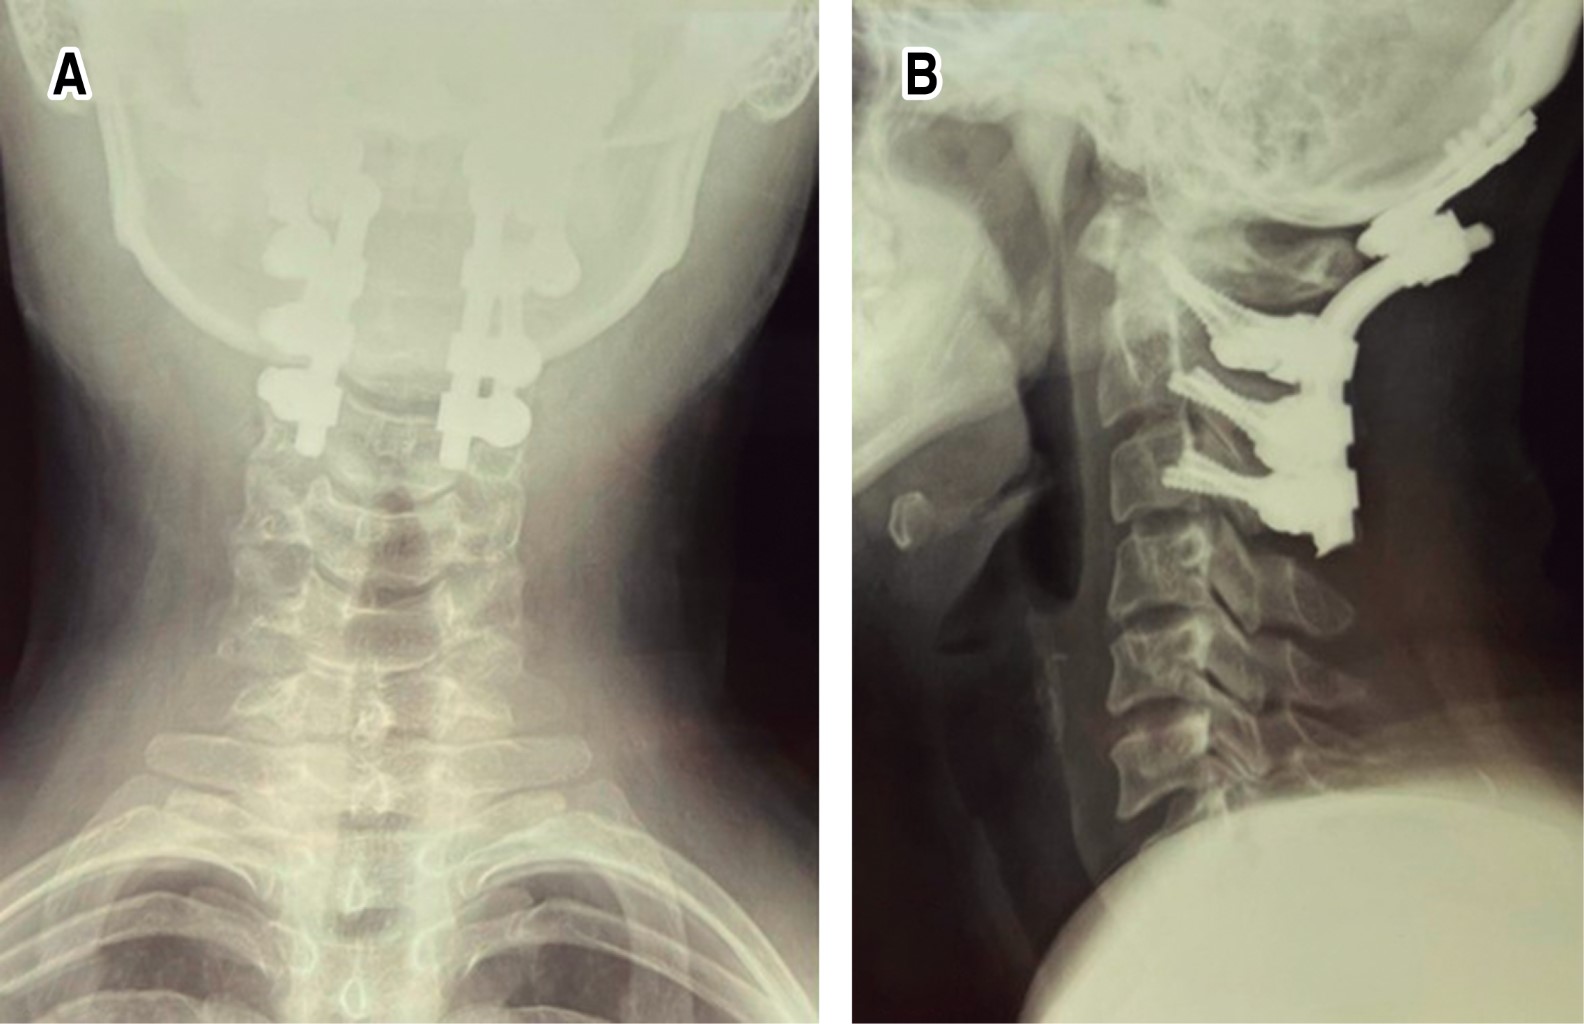

Introduction: injuries to the craniocervical junction with instability secondary to trauma are rare; with complications with a high mortality rate. When both lesions are present; the patient's prognosis for survival and recovery is usually very poor. Surgical treatment for reconstruction of the occipitocervical junction are complex and uncommon procedures; in most cases they have been studied in the treatment of degenerative and rheumatic pathologies. Clinical case: 27-year-old female patient, with combined occipitoatloid-atlantoaxial instability secondary to an accident in a motorcycle-type vehicle; which has multiple injuries. Diagnosis: clinic with neurological deficit; radiological studies of trauma, and axial tomography of the skull and spine, where data of instability at the C0-C1 and C1-C2 levels are evident. Interventions: multidisciplinary management and subsequently occipitocervical reduction and fixation with Harms technique of the injuries due to traumatic vertebral instability; C0-C1, C1-C2 and C2-C3. Follow-up: 9 months after the intervention, with adequate clinical evolution. Conclusions: although there are few publications and guides on the diagnosis, ideal moment of intervention and optimal stabilization method in cases of instability due to trauma, we recommend a multidisciplinary approach. Early diagnosis and treatment directly influence the final prognosis and quality of life of these patients.

Figure 2